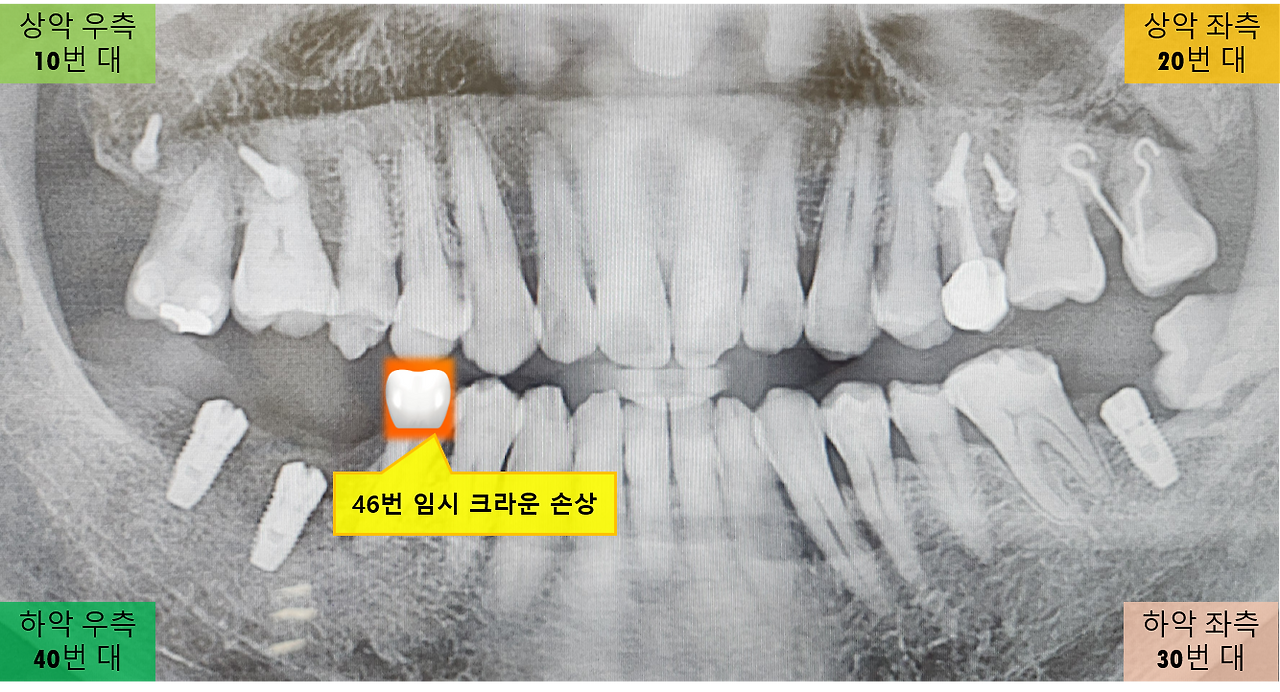

46번 크라운 손상.png [손상된 46번 임시 크라운]

다행스럽게도 임플란트를 위한 임시 크라운(47번과 48번)이 아니라, 바로 이웃한 46번 자연치아의 임시 크라운이 깨진 것이었습니다. 임시 크라운이 깨지는 것을 보니 먼저 옆면이 깨지더니 이후 윗부분이 떨어지더군요. 46번은 자연치아를 다듬어 임시 크라운을 씌운 상태라 다행히 음식을 씹는데 큰 지장은 없었습니다. 덕분에 설 연휴동안 맛있는 음식들을 별 문제없이 마음껏 즐길 수 있었습니다. 만약 임플란트용 임시 크라운이 손상되었다면 어떠했을지 모르겠네요. 임시 크라운이 떨어져 나가면 바로 어버트먼트(Abutment)가 노출될테니, 음식을 씹기는 어려웠을 것이고 추가 손상의 우려때문에 훨씬 고생이 심했을 것입니다.

임시 크라운이 깨졌네요.

오늘은 원래 교정 상태를 점검하러 오는 날이지만, 그보다 더 시급한 문제는 파손된 임시 크라운을 다시 제작하여 붙이기 위해서 입니다. 임시 크라운은 사용 중 파손될 수 있다는 주의를 듣기는 했지만, 막상 깨지니 당황스럽더군요.(임시 크라운은 최종 보철물보다 강도가 약하므로 끈적거리거나 딱딱한 음식은 피해야 합니다).